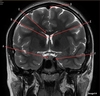

A

Genu Corpus Callosum

B

Splenium Corpus Callosum

C

Pons

D

Cerebellum